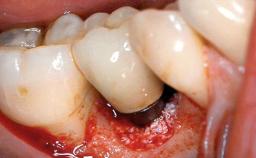

A 65-year-old female patient was referred to the periodontist for assessment and management of implant site 12. Implant 12 had been placed ten years previously and restored with a cemented single crown. The patient was a non-smoker in good general and periodontal health. On examination there were 7 mm probing depths at implant 12 with suppuration and bleeding on probing. The patient was aware of the presence of pus but had no discomfort. A periapical radiograph showed marginal bone loss to approximately the third thread of the implant. Previous radiographs obtained from the referring clinician indicated that there had been progressive bone loss since the implant was restored. A diagnosis of periimplantitis was made.